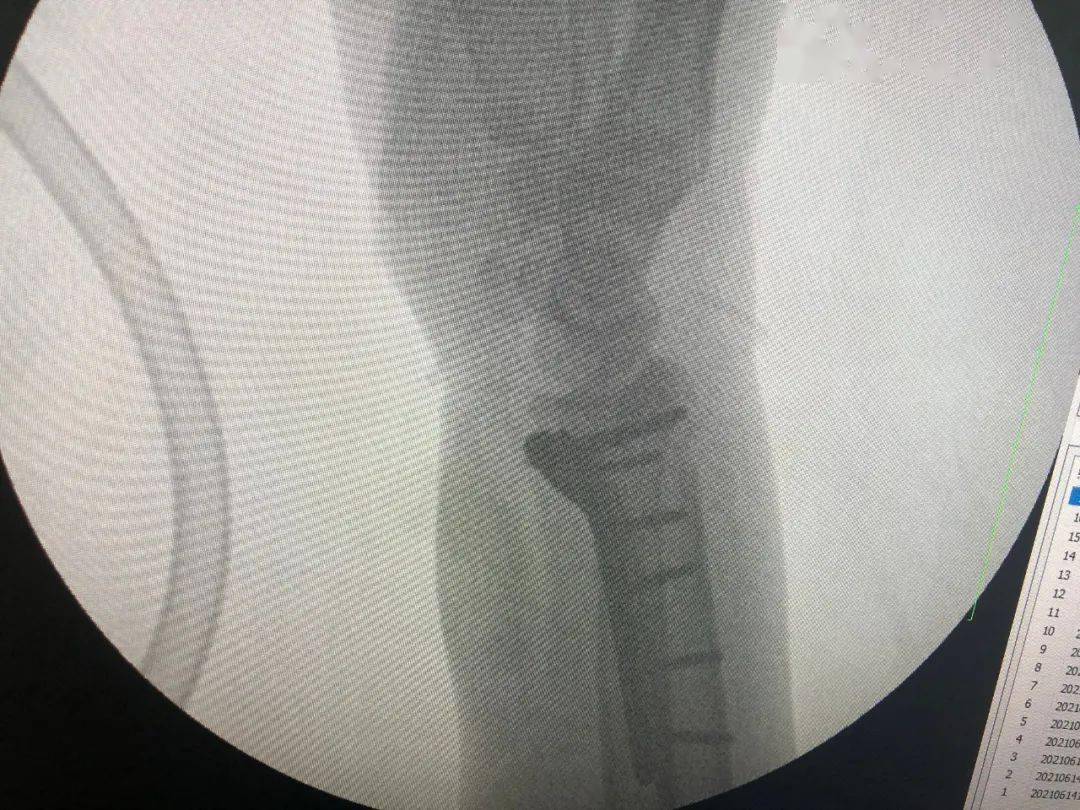

桡骨远端骨折,关节面塌陷:行切开复位钢板内固定术胸腰椎压缩骨折(男

图片尺寸1080x810